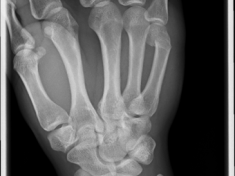

Röntgenbilder